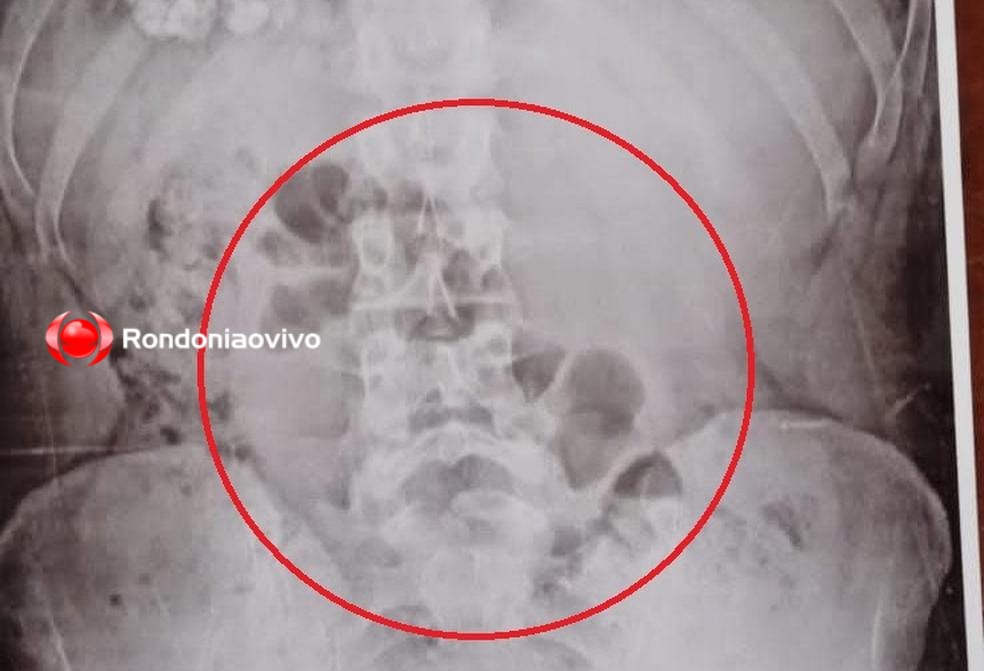

Mulher foi descoberta com a droga no estômago durante revista através do equipamento de raio-X

Foto: Rondoniaovivo